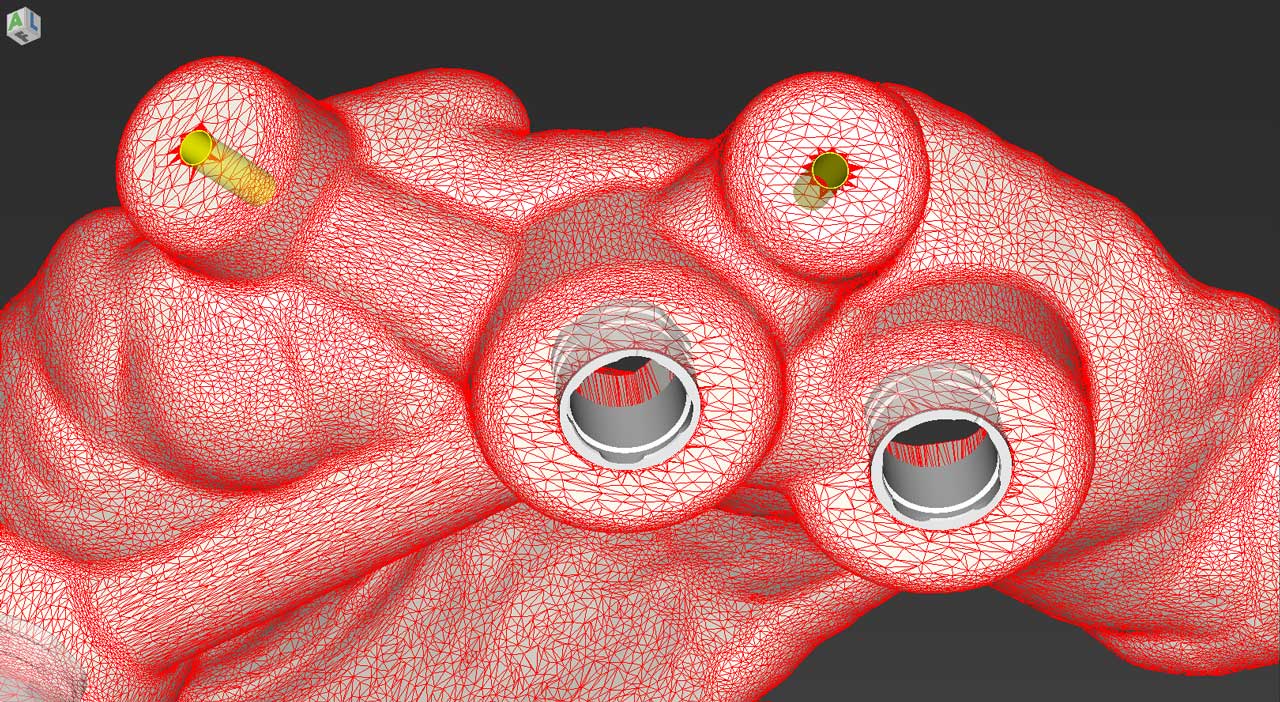

Ψηφιακή Εμφυτευματολογία (Μέρος 1 – ΧΕΙΡΟΥΡΓΙΚΗ) Ασφάλεια & Προβλεψιμότητα στην Εμφυτευματολογία